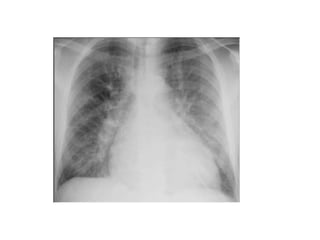

CXR

- Enlarged cardiac silhouette - Heart size normal

- Vascular redistribution - Uniform alveolar infiltrates

- Interstitial thickening - Pleural effusions uncommon

- Perihilar alveolar infiltrates

- Pleural effusions

- Kerley lines

CARDIOGENIC vs NONCARDIOGENIC CARDIOGENICNON-CARDIOGENIC S3 gallop Relatively normal in early stages Elevated JVP Peripheral edema Rales and wheezes on auscultation CXR - Enlarged cardiac silhouette - Heart size normal - Vascular redistribution - Uniform alveolar infiltrates - Interstitial thickening - Pleural effusions uncommon - Perihilar alveolar infiltrates - Pleural effusions - Kerley lines